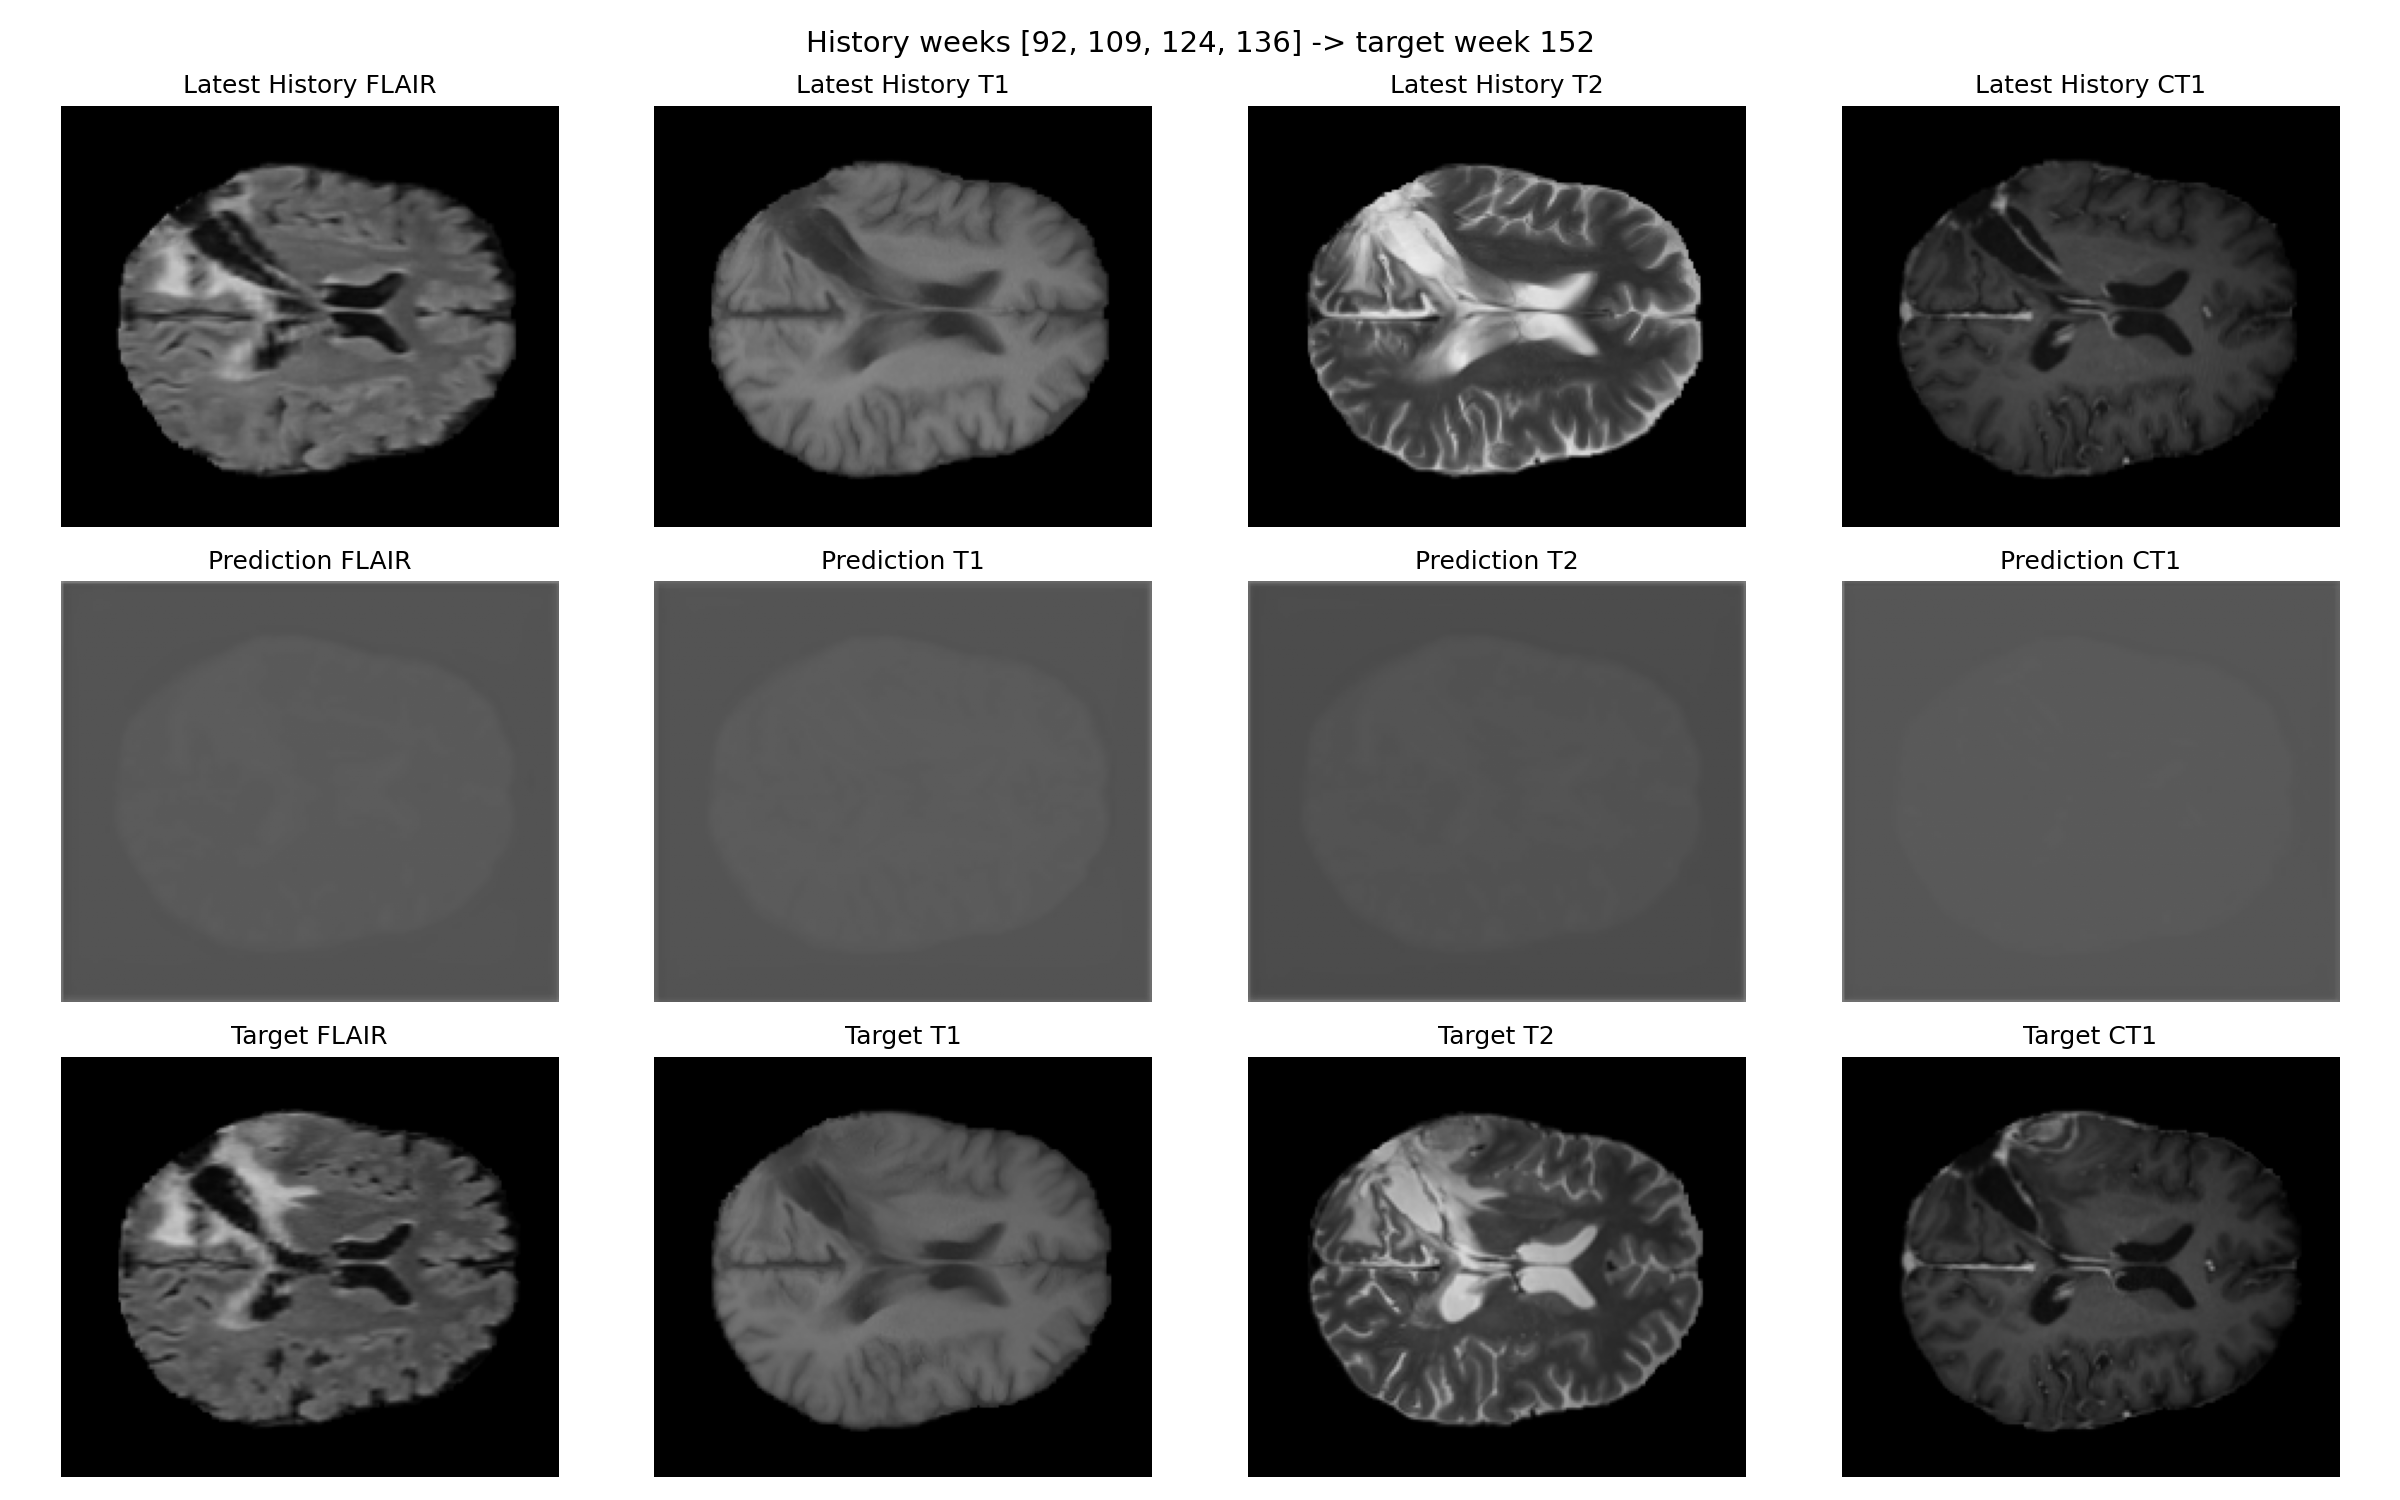

Patient 067

Prediction and target for patient 067

Prediction versus target for week 152.